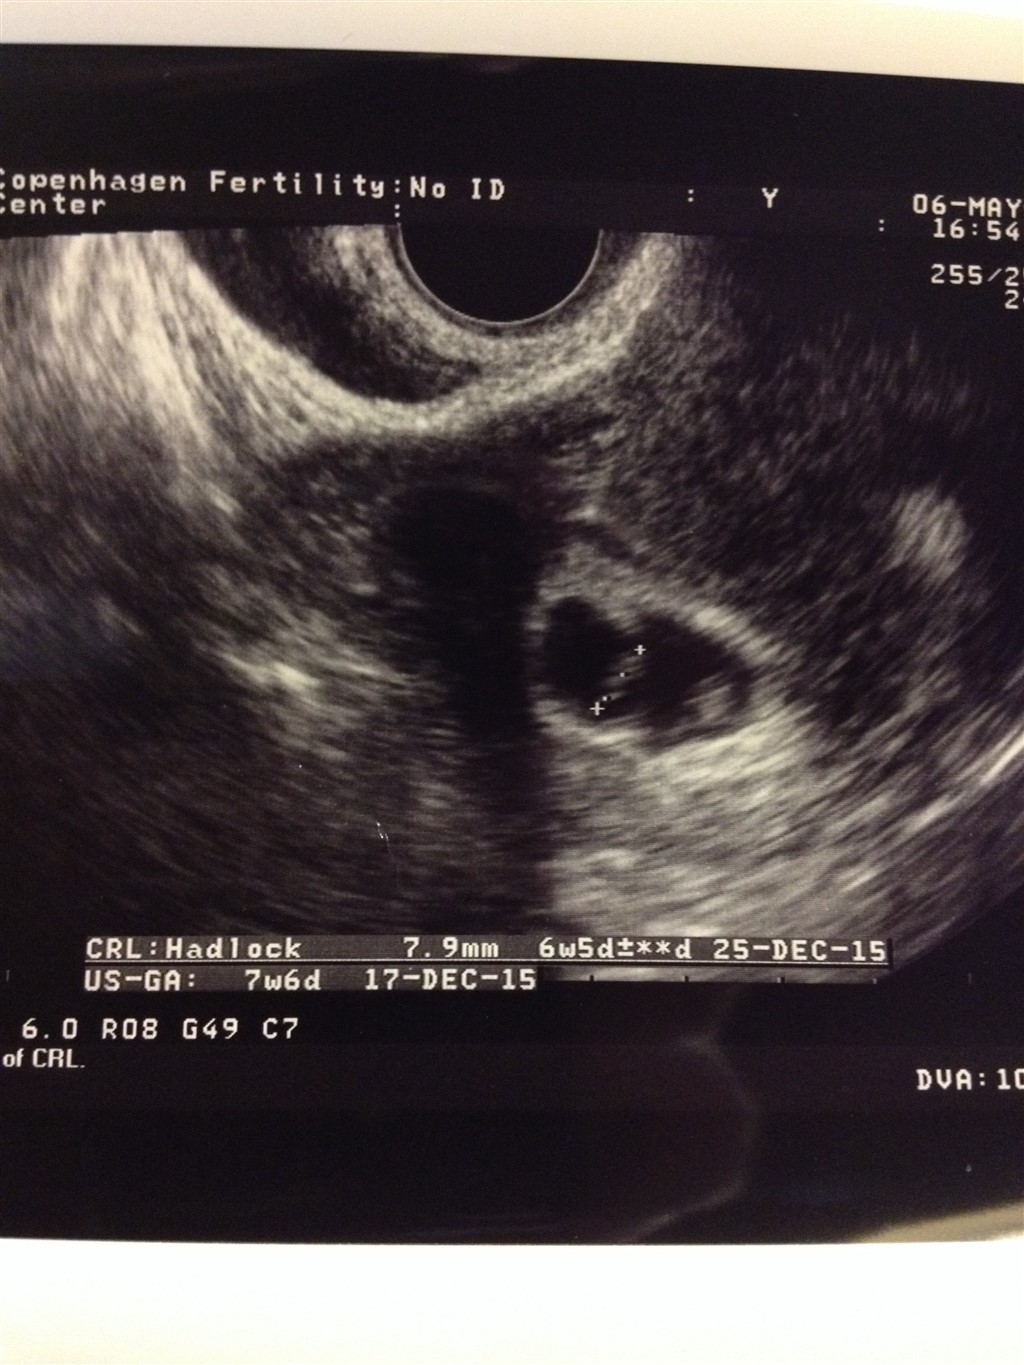

Har fået en scanning 5+6, da jeg troede jeg ville se noget der, men der var ikke særlig meget at se synes jeg. Fostervand tror jeg han sagde og en lille bitte hvid kugle...

Er der overhovedet en chance for jeg alligevel har en lille en derinde?

blev selv scannet al for tidligt på grund at tvivl om terminsdato.

Ved mig var der desværre kun en gestationssæk , den med fostervand i, ved mig manglede "madpakken" og fostersækken, så vær du rigtig glad for du har set den

Du har set det helt Rigtoge, selvom det ikke var meget